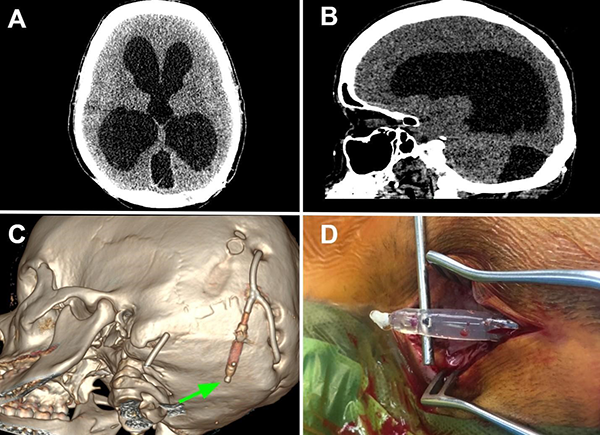

Tras 2 meses, la paciente volvió a consultar en guardia por náuseas, cefalea bifrontal con irradiación holocraneana de intensidad moderada y vómitos. Al examen físico se constató limitación de la mirada superior y colección líquida sobre herida craneal de derivación. Se realizó TC de cerebro con evidencia de ventriculomegalia y desconexión de catéter distal a la válvula (Figura 1). El estudio radiográfico reveló migración caudal del segmento distal del catéter al corazón (Figura 2). El segmento migrado fue rescatado mediante un abordaje endovascular transfemoral, en el cual se enroscó el catéter migrado con un catéter pigtail y se lo desplazó hasta la vena ilíaca primitiva izquierda para luego ser capturado a nivel ilíaco con un lazo trilobulado (Figura 3).

Figura 1. A y B. Corte axial y sagital de TC de cerebro evidenciando marcada hidrocefalia supratentorial. C. Reconstrucción 3D de dicha tomografía, se observa desconexión del catéter distal (flecha verde). Aclaración: sobre mastoides izquierda se evidencia catéter calcificado de válvula previa abandonada. D. Imagen intraquirúrgica con evidencia de desconexión de segmento distal.

Una vez retirado el segmento migrado, se colocó un nuevo catéter distal en el atrio. Luego del procedimiento, la paciente presentó franca mejoría sintomática con resolución del cuadro de cefalea y Parinaud. Se realizó una tomografía de control a los dos días en donde se corroboró la disminución del volumen del sistema ventricular y fue dada de alta deambulando por sus propios medios. En el control ambulatorio, al mes de la cirugía, se mantuvo asintomática, sin nuevos signos de hidrocefalia ni complicaciones asociadas, con un control imagenológico estable (Figura 4).

Figura 4. A y B. Corte axial y sagital de TC de cerebro en segundo día postoperatorio, evidenciándose franca disminución del volumen del sistema ventricular. C y D. Corte axial y sagital de TC de cerebro control al mes de la cirugía, sin cambios.